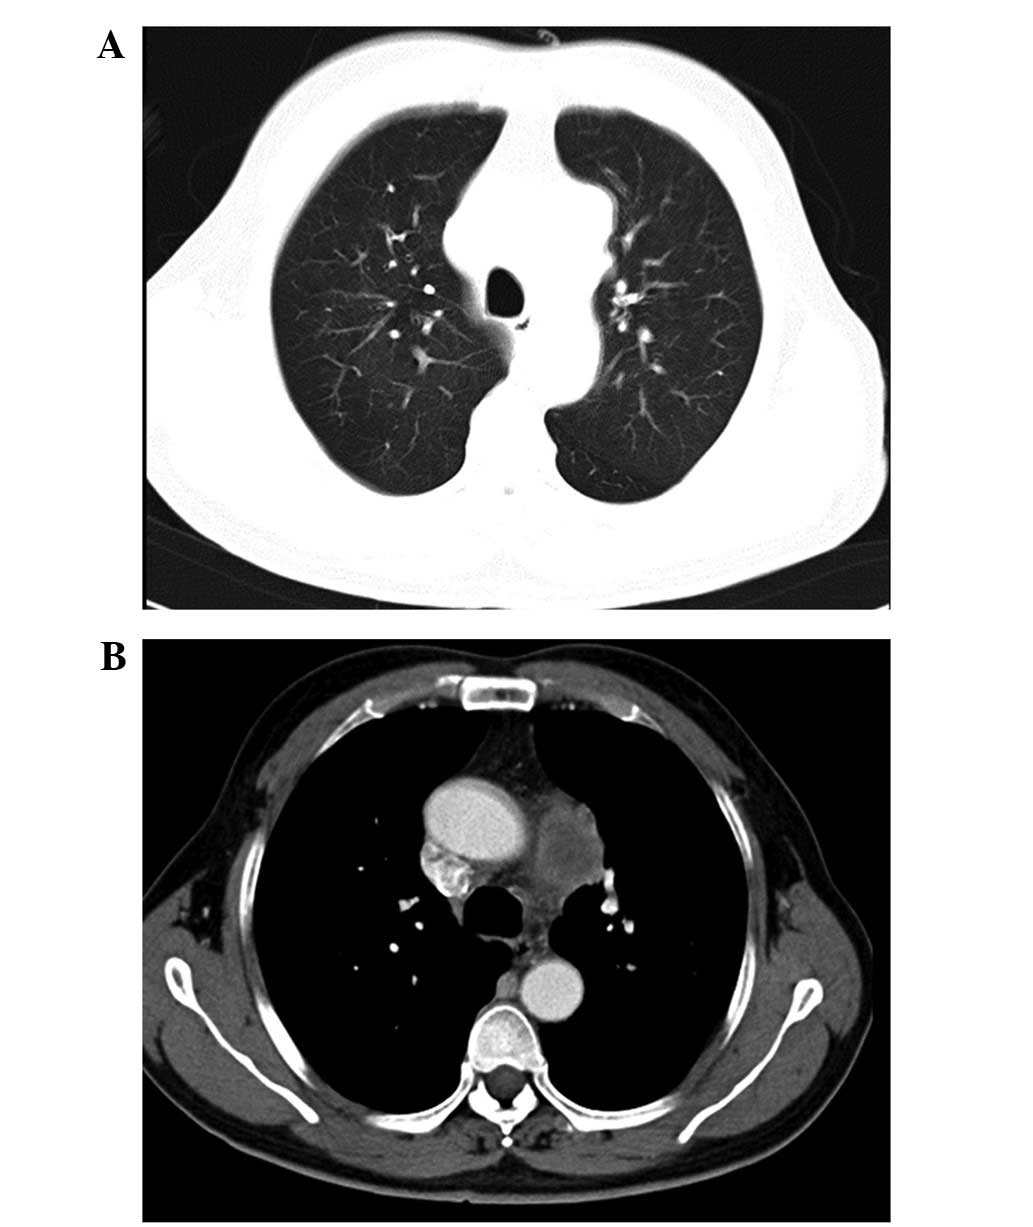

At the initial examination, laboratory results were as follows: Red blood cells, 3.98×1012/l (4–5.5×1012/l); hemoglobin, 118 g/l (120–160 g/l); white blood cells, 4.57×109/l (4–10×109/l); platelets, 121×109/l (100–300×109/l); and erythrocyte sedimentation rate, 23 mm/h (0–15 mm/h). Biochemical examination revealed the following results: Total serum protein, 61.6 g/l (66–87 g/l); albumin, 29.6 g/l (35–54 g/l); globulin, 32 g/l (20–40 g/l); C-reactive protein, 17 mg/l (0–5.0 mg/l); serums carcinoembryonic antigen, 5.12 ng/ml (0–6.5 ng/ml); neuron-specific enolase, 9.45 ng/ml (0–20.0 ng/ml); and CYFRA 21-1, 1.21 ng/ml (0.1–3.3 ng/ml). Chest CT revealed a large lump mass in left upper mediastinum (Fig. 1A and B). Thoracoscopy was performed and revealed that the left pulmonary artery was engulfed by the lump mass. As a result, the surgical resection of the tumor was abandoned. The patient was confirmed with a diagnosis of primary pulmonary synovial sarcoma following the histopathological and immunohistochemical analysis of biopsy specimens via thoracoscopy. Histologically, the lesion was composed of bundles of spindle-shaped cells, with areas of necrosis, sclerosis and hyalinosis (Fig. 2). Immunohistochemically, the tumor cells were positive for epithelial membrane antigen (EMA), CD99, B-cell lymphoma 2 (bcl-2) and vimentin (Figs. 3 and 4), but negative for S-100, SyN, Myo-D1 and CD20. Based on all of these findings, primary pulmonary synovial sarcoma was definitely diagnosed.

Figure 1.

Computed tomography scan showed a large lump mass in left upper mediastinum, but no significant lesion in the left lung. (A) Lung window and (B) mediastinal window.

Radiographic and subsequent CT imaging of the chest are typically conducted as primary investigative measures in the diagnosis of primary pulmonary synovial sarcoma. A chest CT scan showed that the majority of the masses were well-defined and measured >5 cm, displaying heterogeneous enhancement using intravenous contrast materials. Tumors of this type are often calcified and exhibit invasion of the pleura, resulting in pleural effusion (4,11). To the best of our knowledge, involvement of the mediastinum, particularly presenting with a large lump mass in the mediastinum as the sole initial imaging manifestation, in the course of primary pulmonary synovial sarcoma is extremely rare, which may have been a factor in the delayed diagnosis or misdiagnosis. We speculate a number of possible causes: i) The tumor in the present case may have originated in the left pulmonary artery and grew to the left upper mediastinum; or ii) the characteristics of expansive growth, well-defined with coated or fake capsule formation of the tumor resulted in clear delineation between the tumor and the lung.